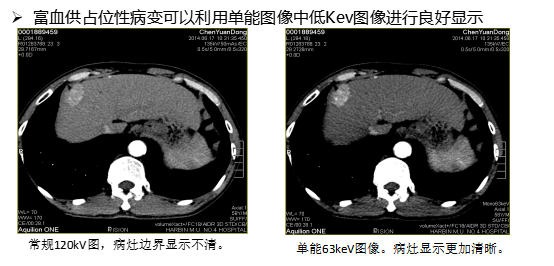

三、能谱单能成像

利用独有的35keV到39kev的低keV图像增加不同组织结构之间的对比 ,有利于等密度病变和小病灶的早期探查、发现,有助于发现乏血供性小肿瘤,显示肿瘤细小供血动脉等 ,可为手术提供依据,如复查栓塞术后效果 ,非常优秀的显示静脉系统,优化动脉成像等。